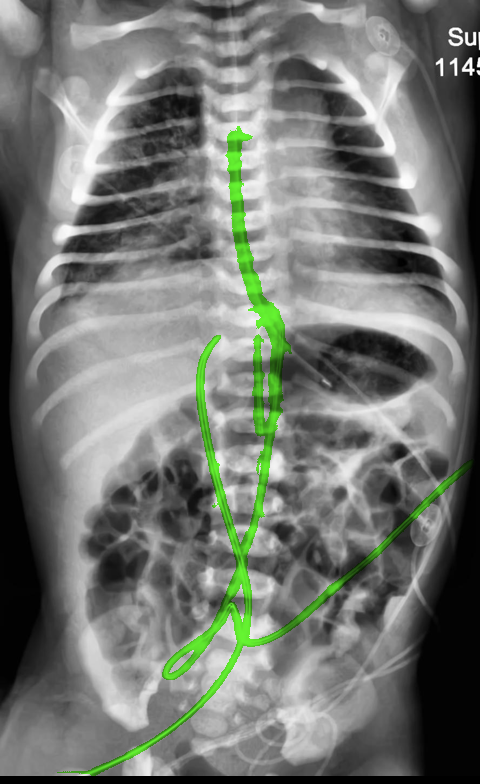

Automated catheter detection is a challenging task. Although most catheters have a radiopaque strip to facilitate detection, the strip may become less apparent depending on the projection angle. Catheters maybe confused by other similar linear structures like ECG leads and anatomy including ribs. Additionally, portions of catheters can be occluded by anatomical structures given that radiographs are a 2D projection of a 3D structure. For example, when a NGT is placed within the oesophagus, the catheter itself becomes less apparent due to the high density of the adjacent vertebrae. Finally, the number and type of catheters that could possibly appear in pediatric X-rays are unknown a priori. The catheters may be intertwined with each other thus making simple line tracing methods fail. Figure 1 gives three sample pediatric X-ray images with some common catheters highlighted in different colors.

To alleviate this annotation problem in catheter detection, we proposed to use X-ray images with simulated catheters by exploiting the fact that catheters are essentially tubular objects with various cross sectional profiles. To be more specific, a synthetic 2D projection of a catheter is generated by first simulating a horizontal catheter profile and then using it as a brush tip to draw along a B-spline path. This generated catheter is then composited with an X-ray image serving as the training data. Another contribution of this work is a segmentation network that can inherently take into account multi-scale information. This network adopts a UNet-style form and contains a recurrent module that can process inputs with increasing scales111Our code is available at https://github.com/xinario/catheter_detection.git.. We have empirically shown that by iterating through the scale space of the input image, higher recall is achieved as compared to using a single scale. Details about the methods are discussed in Section 3. Three sample detection results are shown in Figure 1.

The test dataset is collected locally and only contains frontal chest-abdominal X-rays from patients < 4 weeks old. This is the most common radiograph obtained to confirm placement of catheters such as UACs and UVCs in neonates. Currently, the test set has 35 fully labeled images with different catheter types with sample images previously shown in Figure 1. All the annotated catheters (lines excluding ECG leads) are treated as the same class in the detection.